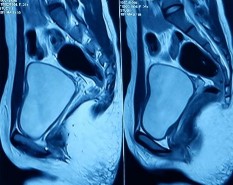

Hình ảnh trên phim chụp cộng hưởng từ vùng tiểu khung cho thấy 2 bệnh nhân hoàn toàn không quan sát thấy tử cung, 2 bệnh nhân có tử cung có kích thước nhỏ (10x29mm và 13x18mm), không phân biệt rõ lớp cơ và niêm mạc, 1 bệnh nhân có cấu trúc dải xơ nối liền hai buồng trứng nghi là dấu vết của tử cung thiểu sản. Một bệnh nhân còn lại có cấu trúc giống sừng nguyên thủy của tử cung ở vị trí bên cạnh buồng trứng hai bên. Có 4/6 bệnh nhân không quan sát được âm đạo, 1 bệnh nhân âm đạo là một dải mảnh, 1 bệnh nhân có âm đạo cụt, không liên tiếp với tử cung.

Hình 3.2. Hình ảnh phim cộng hưởng từ vùng tiểu khung

Trên kết quả siêu âm và cộng hưởng từ không phát hiện bất thường nào khác ở buồng trứng, thận, và các cơ quan khác.